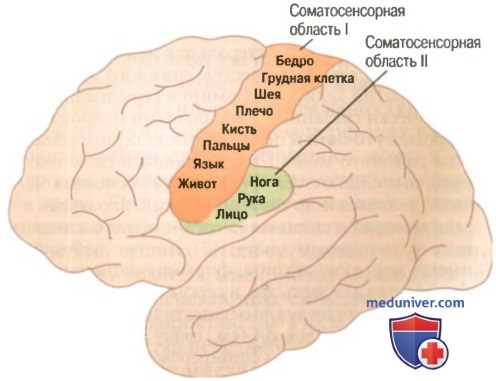

Схема чувствительных зон новой коры мозга